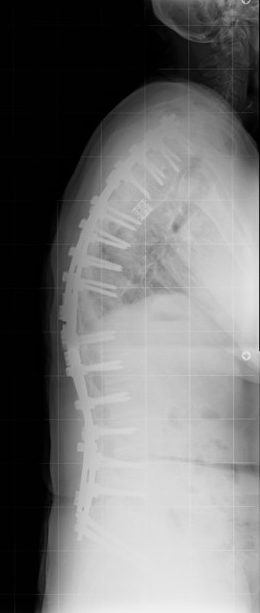

63 Yaşında Kadın Hasta

Ameliyat Sonrası